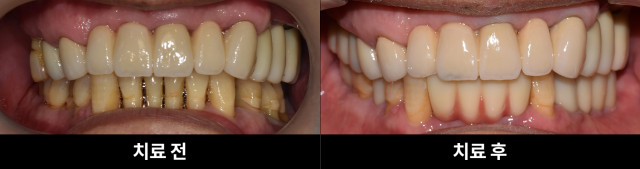

[200616 ~ 211018] 강**님 치료과정